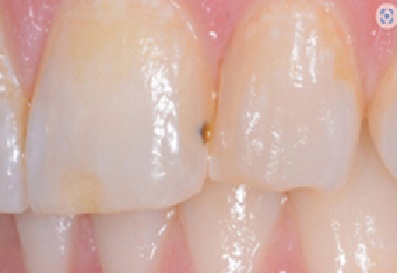

2. Плями і дефекти реставрації

Якщо бульбашка залишається на поверхні композиту, вона утворює заглиблення, де з часом накопичується пігмент.

Це призводить до появи темних плям і естетичних недоліків, що можуть стати причиною невдоволення пацієнта або навіть його переходу до іншого лікаря.